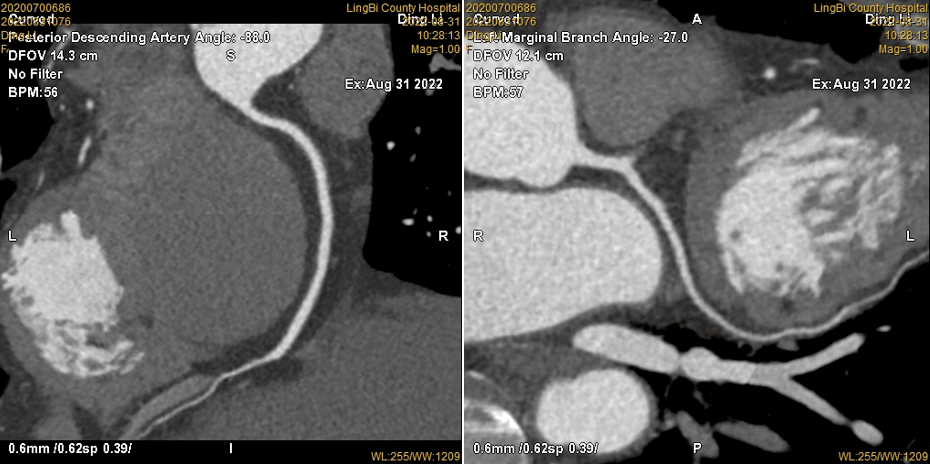

2.心脏冠状动脉成像和心功能评价:检查无创,整个心脏高分辨率的检查仅需5秒钟,可看到完整、清晰的三维立体冠状动脉图像,为冠心病的筛查及早期诊断提供准确可靠的影像依据,对冠状动脉内支架置入、搭桥的术后的患者,可以清晰观察到支架和桥血管的情况;准确对心肌病、瓣膜病、心包疾患、心脏肿瘤、先天性心脏病、大血管疾病等各种心脏大血管疾病进行影像诊断与评价。

(心脏CTA部分图片展示)